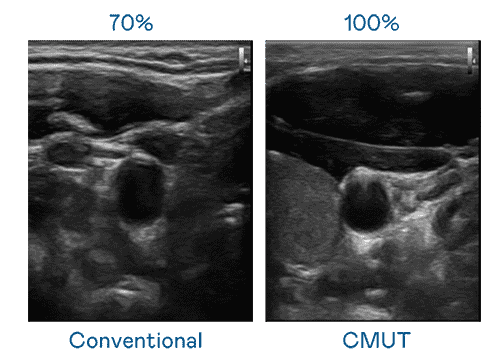

CMUT 技术是一种用电容式微机电元件来产生超音波讯号的技术。。与传统 PZT 压电式技术相比,,CMUT 频宽增加 30%,,,更宽频的超音波讯号让影像解析度大幅提升,,,是实现高影像品质医疗超音波扫描、、促进精准医疗发展的关键技术。。

大频宽带来超清晰影像

超音波影像的解析度高低,,首先取决于探头能发出的讯号频宽。。。。尊龙集团 CMUT 可提供高清晰的超音波讯号,,,提供高频宽、、、、高灵敏度、、、影像纹理细节更高的超音波影像,,协助医护人员缩短影像判读时间及利用精准的医疗影像进行诊断。。。。